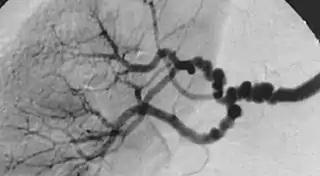

![]() Oclusiones sucesivas de la arteria renal por displasia fibromuscular. | ||

La causa más frecuente de la hipertensión renal es la ateroesclerosis seguido por displasias fibromusculares[1] obliterando la vasculatura extra o intrarenal. La oclusión debe ser suficiente para limitar el flujo glomerular como para activar los mecanismos que elevan la presión arterial a los niveles y duración característicos de la hipertensión renovascular.[2]